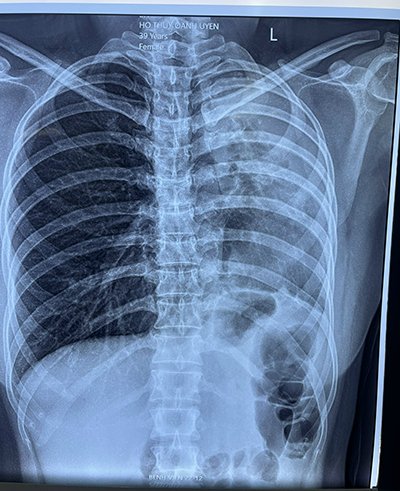

Sau khi khám và kiểm tra lâm sàng, bác sĩ khoa Ngoại tổng quát chẩn đoán: Bệnh nhân viêm ruột thừa cấp/ xẹp phổi trái. Lao phổi cũ.